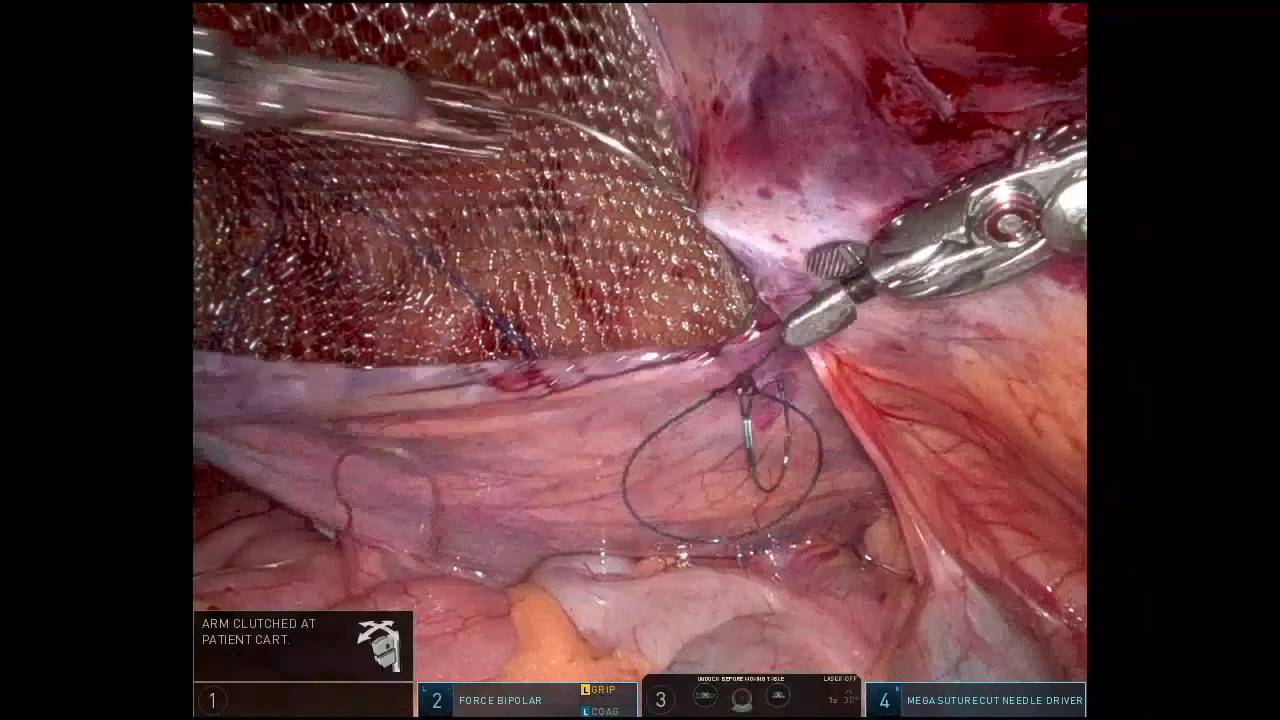

Dr. Malcher | Robotic repair of incarcerated inguinal hernia using CO2 asperation tip

Doctor(s): Dr. Malcher Description of of the case: Robotic repair of incarcerated inguinal hernia using CO2 asperation tip Products Used: Ventralight™ ST Mesh [...]